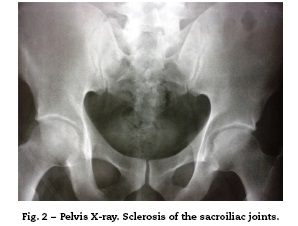

The first observers considered an acute myocardial infarction with ST elevation, reason by which they decided to carry out thrombolysis with alteplase, with improvement of the precordial pain and reduction in the ST segment in the control post-thrombolysis EKG. The paraclinical tests showed: initial troponin of 2.88ng/mL (positive>0.5); second control troponin of 6.53ng/mL and third troponin of 14.7ng/mL. The TT echocardiogram showed a concentric hypertrophic cardiomyopathy and hyperdynamic myocardium. LVEF: 70%. Mild inferior hypokinesis. PSP: 33 mmHg. Normal atria. Mildly dilated ascending aorta. The patient was taken to coronary angiography, which reported coronary arteries without lesions. During his evolution the patient referred lumbosacral pain, and for this reason it was requested a pelvic radiograph, which showed findings suggestive of grade 2 sacroiliitis (Fig. 2).